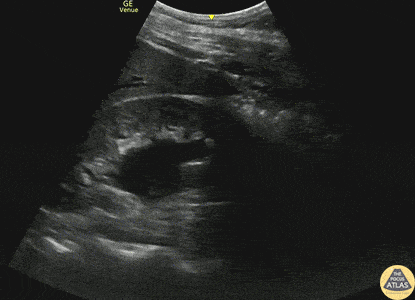

Renal/GU - Moderate Hydronephrosis

30s M with no past medical history presented with acute onset right sided flank pain. POCUS demonstrated moderate hydronephrosis of the right kidney with evidence of hydroureter as well. Moderate hydronephrosis is seen here with distension of the renal pelvis as well as distension of most of the renal calyces, with intact renal cortical thickness. This patient had his symptoms controlled and was able to be discharged. Dr. Mark Serpico, PGY3 Denver Health Residency in Emergency Medicine